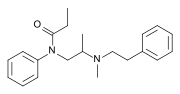

The first fully synthetic opioid was meperidine (later demerol), found serendipitously by German chemist Otto Eisleb (or Eislib) at IG Farben in 1932.[228] Meperidine was the first opiate to have a structure unrelated to morphine, but with opiate-like properties.[199] Its analgesic effects were discovered by Otto Schaumann in 1939.[228] Gustav Ehrhart and Max Bockmühl, also at IG Farben, built on the work of Eisleb and Schaumann. They developed "Hoechst 10820" (later methadone) around 1937.[230] In 1959 the Belgian physician Paul Janssen developed fentanyl, a synthetic drug with 30 to 50 times the potency of heroin.[211][231] Nearly 150 synthetic opioids are now known.[228]

- Fully synthetic opioids: such as fentanyl, pethidine, levorphanol, methadone, tramadol, tapentadol, and dextropropoxyphene;

Diphenylpropylamine derivatives